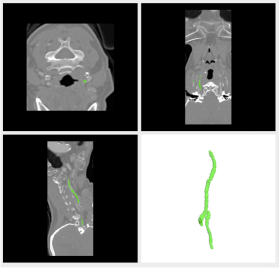

3.1.6 Olfactory Projection Fibers (OPF)

The OPF dataset is actually not from a vascular system, but from a nervous fibers network of the olfactory system. This, of course, hinders the detection of the vascular network (the use of a more appropriate model for vesselness would be advisable), albeit good results were achieved. The dataset is available at the DIADEM (short for Digital Reconstruction of Axonal and Dendritic Morphology) challenge website diadem, which was a competition for evaluating algorithmic methods for automated neuronal tracing.

OPF are network-like structures, but the inner part, corresponding to the lumen in vessels, are not exactly homogeneous and therefore the Gaussian mixture model proposed for vesselness evaluation, delivers low likelihood values. Still, it is possible to take advantage of the structure and segment at least part of the network.

We used this non-vascular network dataset in our experiments mainly because of its reference data, which allowed us to evaluate our method quantitatively. For this, we used the evaluation tool proposed for the DIADEM challenge.

The obtained results are summarized in Table 1, which allows for a comparison of our method with other works. In the table we compare with turetkenneuro2011; turetkencvpr2012, but the interested reader can refer to the challenge website to check other methods results. The results obtained are comparable with the ones obtained by methods designed for segmenting nervous fibers networks. This is encouraging and we believe that a more suited metric for nervous fibers (instead of the proposed vesselness) would improve substantially the results, even though this is not in the scope of this paper. Figure 20 gives a visual feedback of the results obtained in one of the available datasets.